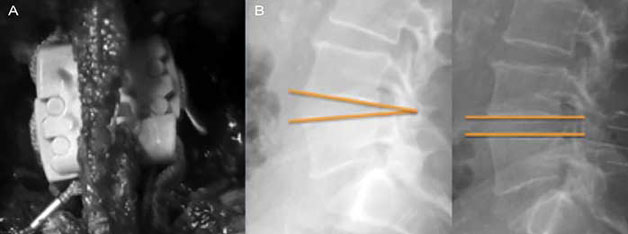

En los dos grupos, los cambios radiológicos en la columna lumbar después de la implantación de el espaciador interespinoso mostraron corrección de la lordosis en 15%, aumento del diámetro del canal en 18%, aumento de diámetro de foramen 25% y aumento de el espacio intervertebral posterior 18%, manteniéndose dicha mejoría a los 6, 12 y 24 meses de control (figura 1).